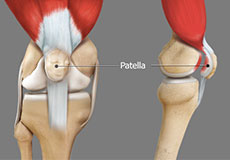

The two femoral condyles form a groove on the front (anterior) side of the knee called the patellofemoral groove. A small bone called the patella sits in this groove and forms the kneecap. It acts as a shield and protects the knee joint from direct trauma.

Patellar Instability

Any damage to the supporting ligaments may cause the patella to slip out of the groove either partially (subluxation) or completely (dislocation). This misalignment can damage the underlying soft structures such as muscles and ligaments that hold the kneecap in place.

Patellofemoral Instability

Patellofemoral instability means that the patella (kneecap) moves out of its normal pattern of alignment. This malalignment can damage the underlying soft structures such as muscles and ligaments that hold the knee in place.

Recurrent Patella Dislocation

The patella (kneecap) is a small bone that shields your knee joint. It is present in front of your knee, on a groove called the trochlear groove that sits at the junction of the femur (thighbone) and tibia (shinbone).